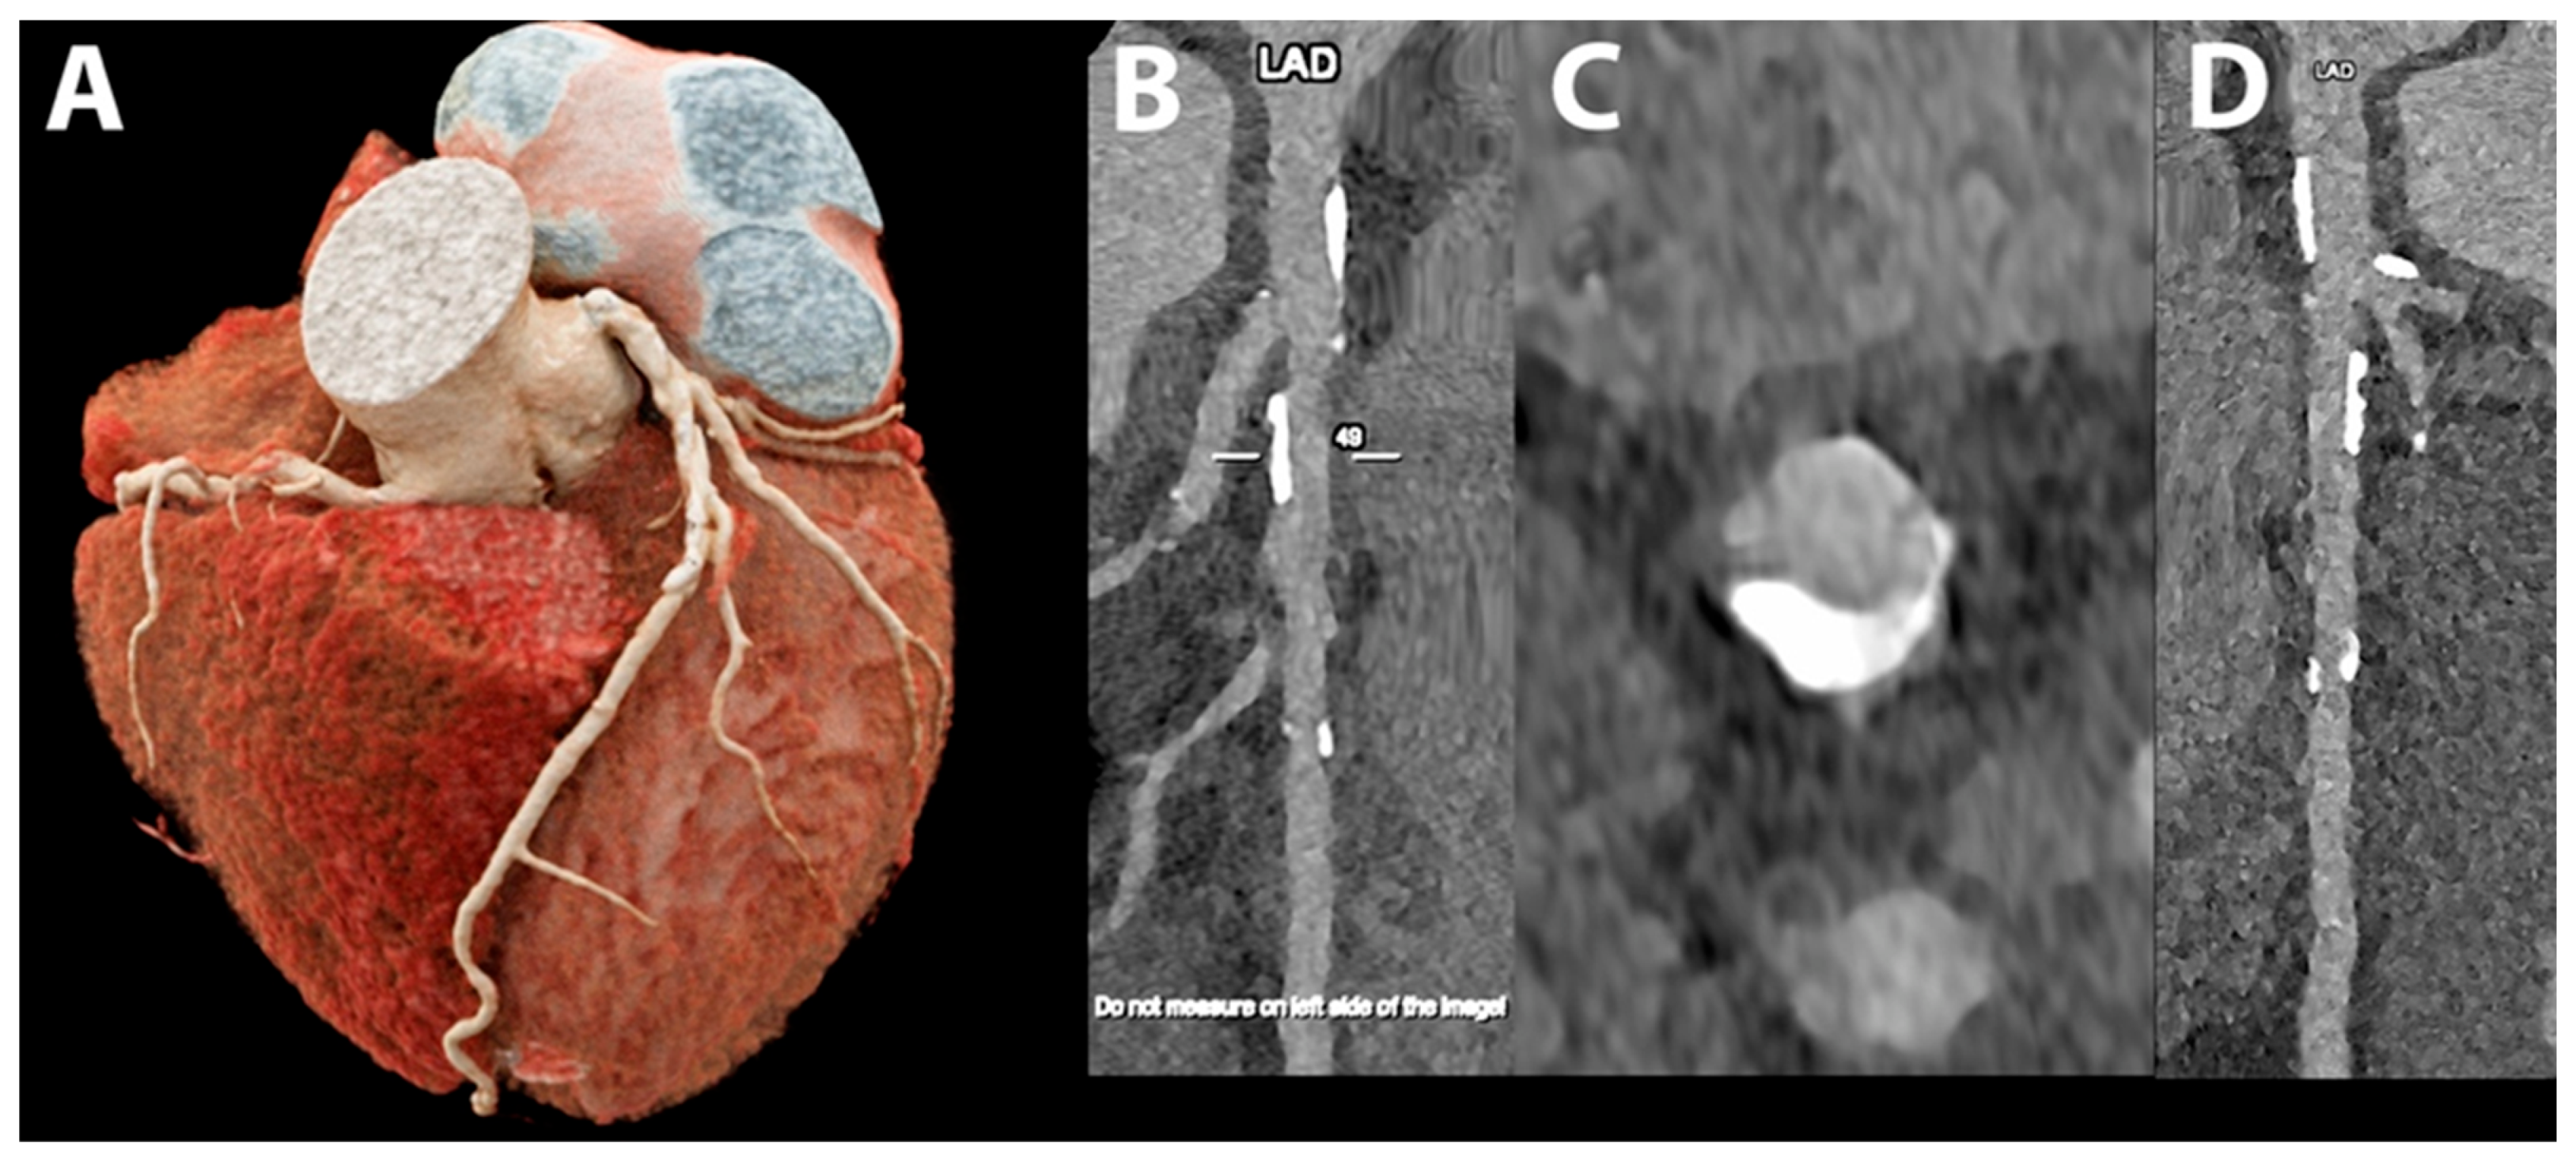

5.4. Coronary Artery Stenting

- Mannil, M.; Hickethier, T.; von Spiczak, J.; Baer, M.; Henning, A.; Hertel, M.; Schmidt, B.; Flohr, T.; Maintz, D.; Alkadhi, H. Photon-Counting CT: High-Resolution Imaging of Coronary Stents. Investig. Radiol. 2018, 53, 143–149. [Google Scholar] [CrossRef]

- Symons, R.; De Bruecker, Y.; Roosen, J.; Van Camp, L.; Cork, T.E.; Kappler, S.; Ulzheimer, S.; Sandfort, V.; Bluemke, D.A.; Pourmorteza, A. Quarter-millimeter spectral coronary stent imaging with photon-counting CT: Initial experience. J. Cardiovasc. Comput. Tomogr. 2018, 12, 509–515. [Google Scholar] [CrossRef] [PubMed]

- von Spiczak, J.; Mannil, M.; Peters, B.; Hickethier, T.; Baer, M.; Henning, A.; Schmidt, B.; Flohr, T.; Manka, R.; Maintz, D.; et al. Photon Counting Computed Tomography With Dedicated Sharp Convolution Kernels: Tapping the Potential of a New Technology for Stent Imaging. Investig. Radiol. 2018, 53, 486–494. [Google Scholar] [CrossRef] [PubMed]

- Rajagopal, J.R.; Farhadi, F.; Richards, T.; Nikpanah, M.; Sahbaee, P.; Shanbhag, S.M.; Bandettini, W.P.; Saboury, B.; Malayeri, A.A.; Pritchard, W.F.; et al. Evaluation of Coronary Plaques and Stents with Conventional and Photon-counting CT: Benefits of High-Resolution Photon-counting CT. Radiol. Cardiothorac. Imaging 2021, 3, e210102. [Google Scholar] [CrossRef] [PubMed]

- Boccalini, S.; Si-Mohamed, S.A.; Lacombe, H.; Diaw, A.; Varasteh, M.; Rodesch, P.A.; Villien, M.; Sigovan, M.; Dessouky, R.; Coulon, P.; et al. First In-Human Results of Computed Tomography Angiography for Coronary Stent Assessment With a Spectral Photon Counting Computed Tomography. Investig. Radiol. 2022, 57, 212–221. [Google Scholar] [CrossRef] [PubMed]

- Bratke, G.; Hickethier, T.; Bar-Ness, D.; Bunck, A.C.; Maintz, D.; Pahn, G.; Coulon, P.; Si-Mohamed, S.; Douek, P.; Sigovan, M. Spectral Photon-Counting Computed Tomography for Coronary Stent Imaging: Evaluation of the Potential Clinical Impact for the Delineation of In-Stent Restenosis. Investig. Radiol. 2020, 55, 61–67. [Google Scholar] [CrossRef] [PubMed]